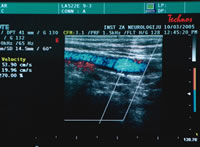

ZVUK KRVNIH SUDOVA |